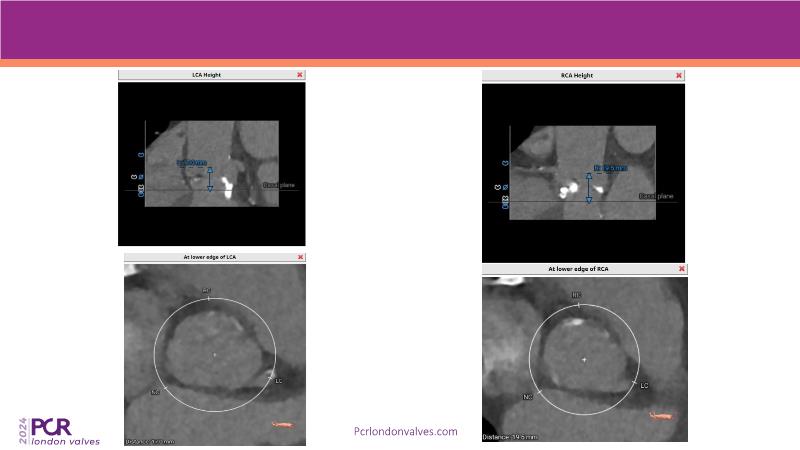

Watch this session to explore expert insights into best-in-class TAVI practices, from pre-procedural imaging and treatment strategy to procedural tips and post-procedural management. Learn from a compelling case study of an 88-year-old male patient with severe symptomatic aortic stenosis treated with the innovative MyVal Octapro THV. Discover key findings from the Landmark RCT sub-group analysis and delve into the unique scientific and design philosophy of MyVal Octapro, along with its real-world clinical potential.

- To learn from the experts best-in-the-class TAVI practice: pre-procedural (Imaging, sizing rationale, treatment strategy), procedural tips and tricks and post-procedural management